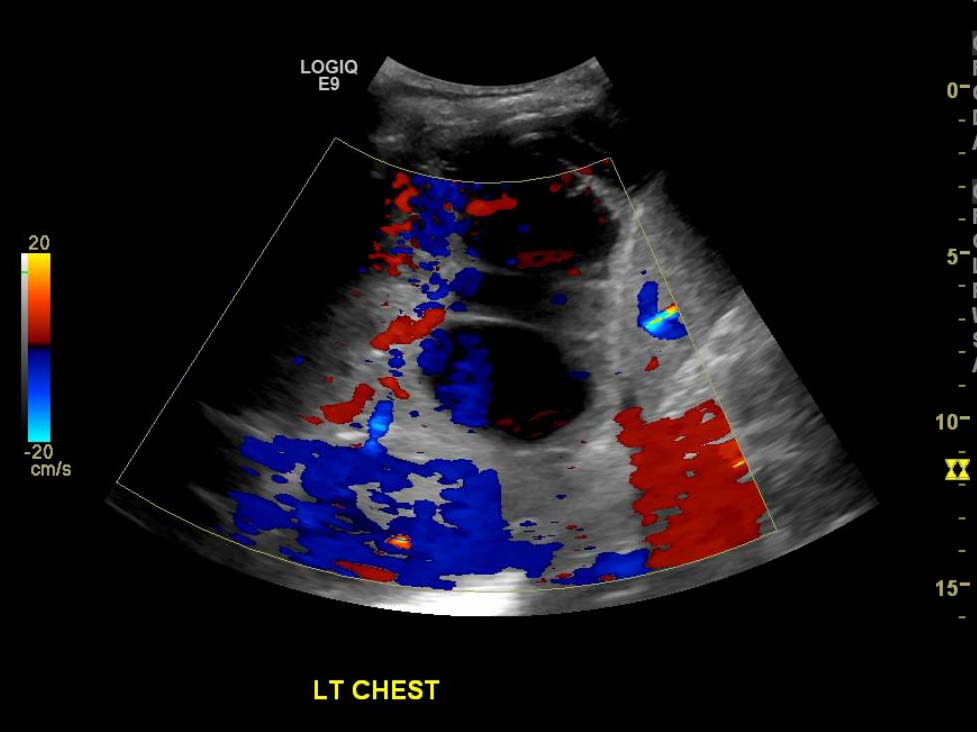

- Large, complex, multiseptated left pleural fluid collection

Large, complex, multiseptated left pleural fluid collection with adjacent airspace consolidation, concerning for pneumonia and empyema. No discernible right pleural effusion.

- Ultrasound can be very useful in evaluating pleural fluid collections as it is more sensitive for detecting pleural fluid than radiography and can be used for procedural planning and guidance

- Worry about a complicated effusion (which may represent empyema, hemothorax, or malignant effusion depending on the clinical scenario) if the fluid collection has hyperechoic areas or if it contains internal septations